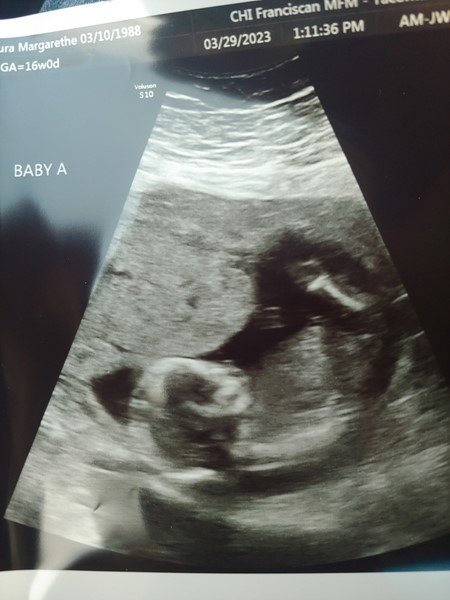

March 29th

Baby A

Baby B

We just got back from the Doctor with ok news. Baby B still does have some fluid and a strong heartbeat. Baby A is doing great, moving around, and revealed himself to be a boy! The risks are still high to both though, especially B. Even if Baby B continues to survive, the cramped quarters could ruin lung and muscle development such that the baby dies shortly after being delivered. However, baby B actually does have some fluid, about 2.15 cm vs 6.5cm of baby A. Our second doctor said that's actually not bad, and most of the lung problems occur with 1cm or less. So good news there. The biggest risk is that infection could happen anytime, and would threaten the lives of all three. Please pray that infection holds off and B's sack refills, or at least that B has enough to move and breath. The plan the doctor gave us was to stay as we are on light duty at home for 7 more weeks, at which time Laura will go to the hospital, where she'll remain on bed rest for the rest of the pregnancy. The best scenario is that she can hold out till 38 weeks, which would be late August, about three months into hospitalization. Anything after 28 weeks would be far better than before 28 weeks. This is all going to be really long and really difficult, and could end in tragedy or mixed results, but the chances of saving one or both are high enough to where we both feel like we can handle it, particularly with all the help we're receiving. Please feel free to share this however you see fit. We want to be able to encourage other people as we go through all this, even as we in turn rely on God through other people to sustain our souls.